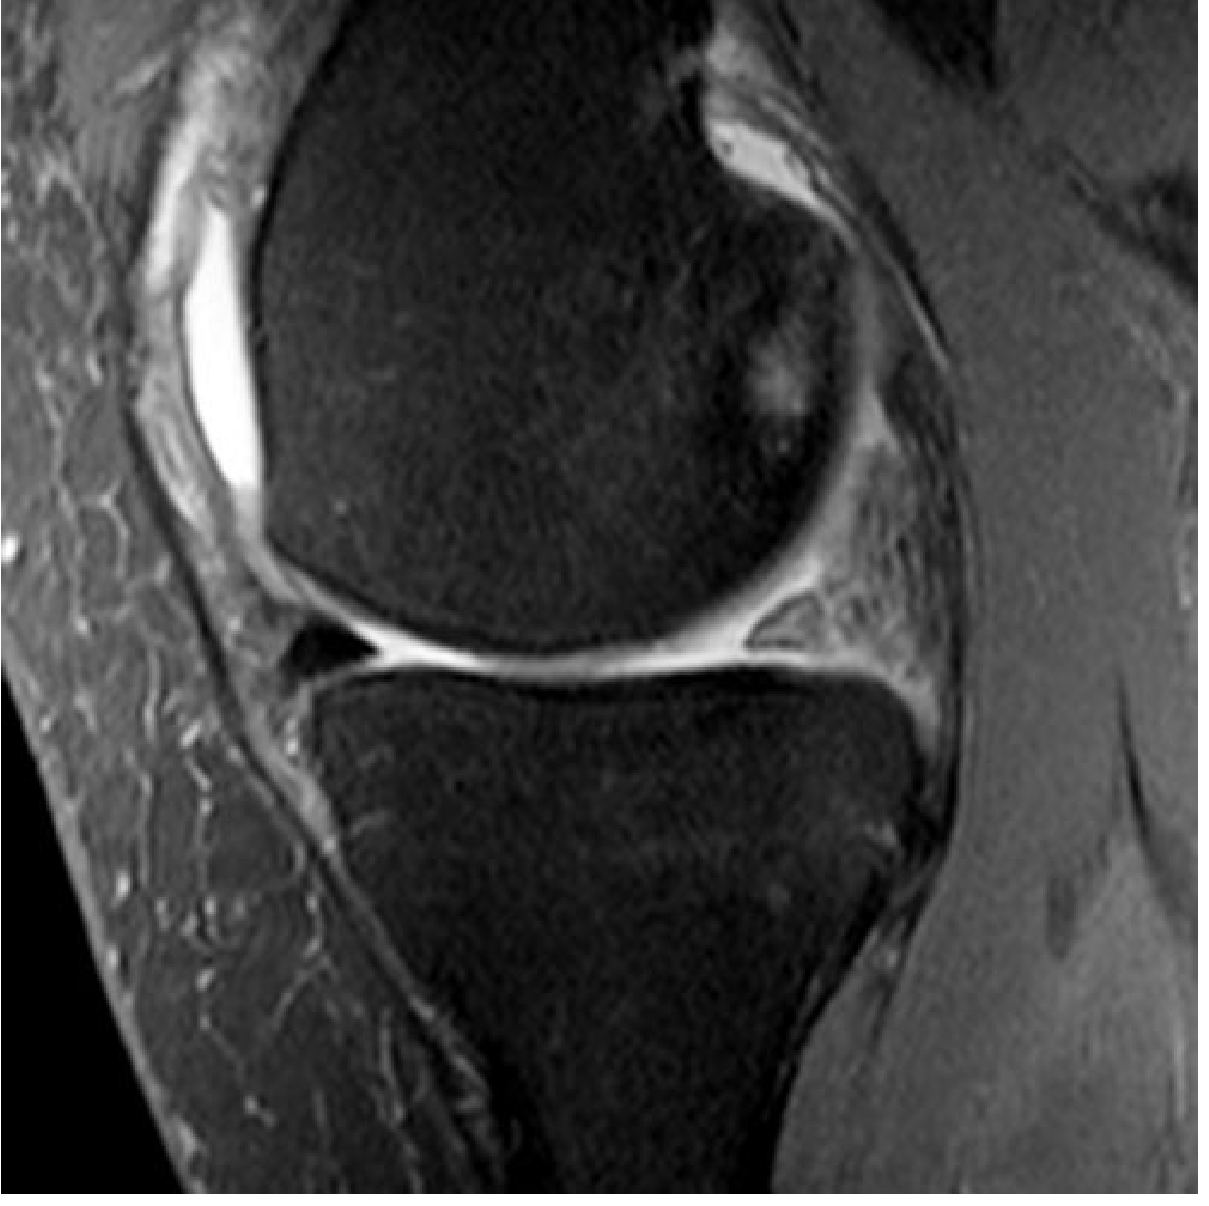

MRI is the modality of choice — detects the tear and associated ligamentous/cartilage injuries.

Coronal MRI showing medial meniscus tear

Coronal MRI of the knee showing a medial meniscus tear (Gray's Anatomy for Students)

• Plain radiographs and CT cannot diagnose meniscal tears

• Arthroscopy remains the gold standard for diagnosis and is simultaneously therapeutic